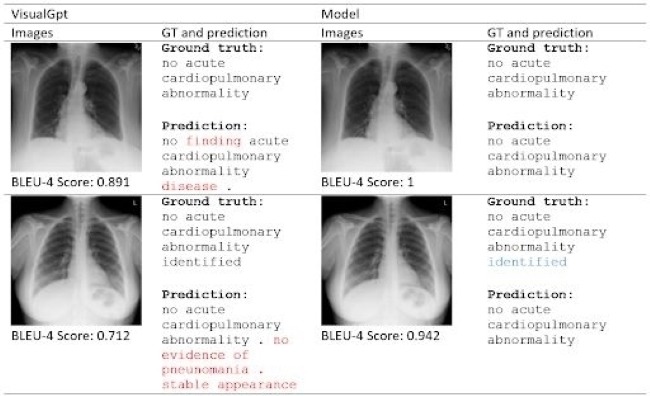

Model data laporan medis citra paru-paru menggunakan teknik Generative Pre-trained Transformer (GPT)

Tak hanya itu, perempuan berhijab tersebut juga menghadirkan kebermanfaatan lain dari keilmuannya tersebut dalam bentuk medical image captioning. Penelitian yang menggunakan teknik Generative Pre-trained Transformer (GPT) tersebut ditujukan untuk dapat membuat laporan medis dari citra sinar X paru-paru.

Pada teknik ini diperlukan metode pengolahan data menggunakan proses encoder-decoder. Dalam proses tersebut, data yang sebelumnya berbentuk citra akan diolah sedemikian rupa sehingga menghasilkan deskripsi teks yang akurat. Dengan hasil tersebut, dapat membantu dokter dalam melakukan penulisan laporan medis dengan tingkat kekeliruan yang rendah. “Selain itu, teknik ini dapat menjadi alternatif pada situasi kekurangan ahli profesional,” ujarnya.